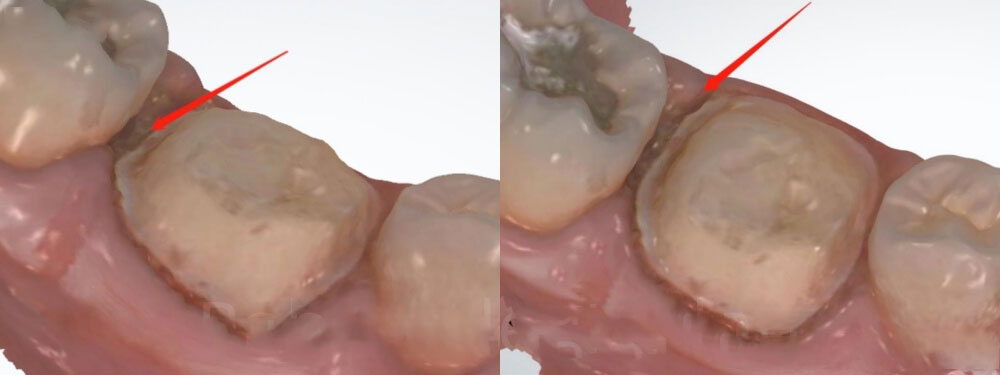

3. Checking the new digital scan

Now let’s look at the new scan. The margin is very clear this time. The dentist cleaned blood and saliva. We believe the dentist used gum retraction cord before oral scanning. Now we can see that the distal margin of the new scan is a lot deeper than that of the first-time scan. This explains why the distal margin of the old crown was open.

Clear margin for dental crown